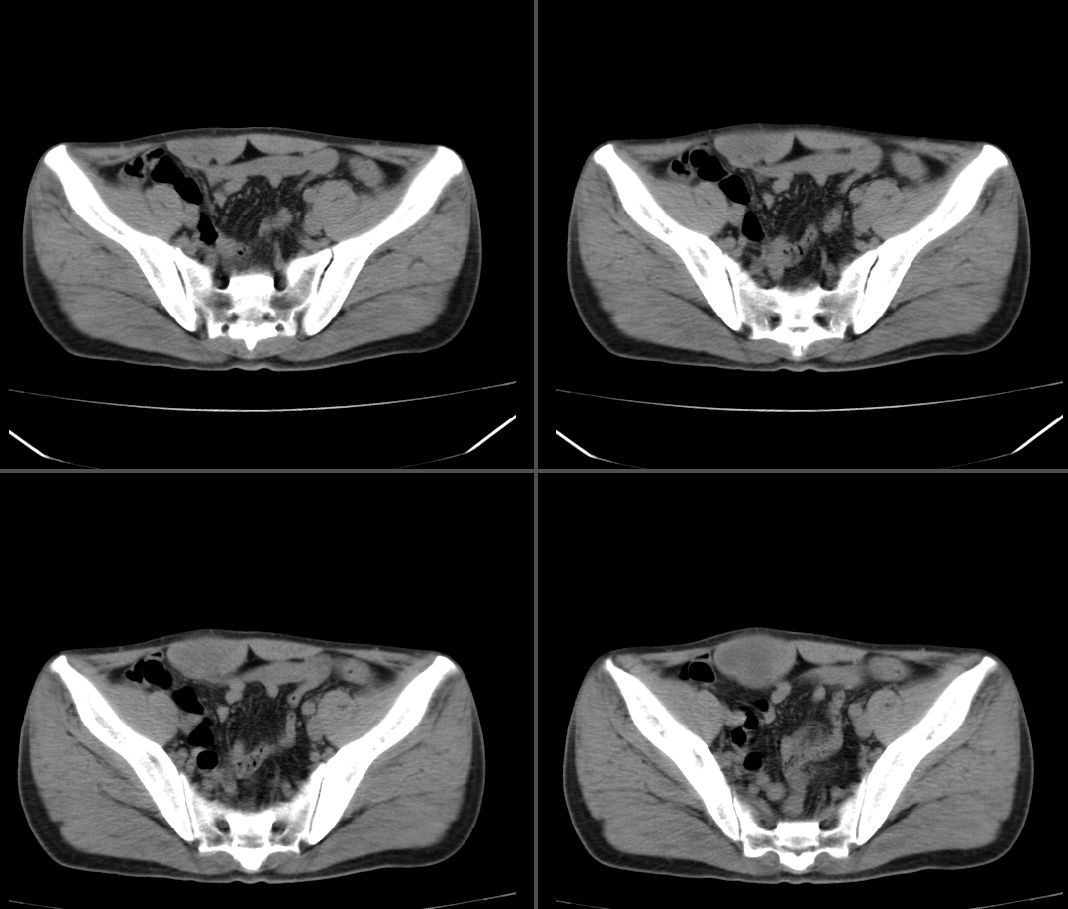

定位:右腹直肌鞘下部

病灶特点:分界清,边缘光整,囊性密度,病灶成长椭圆形,病灶处腹直肌受压萎缩,病灶与膀胱处有相似密度管状灶(该征象因肠道未作准备,不能确切)

拟诊:1.淋巴管囊肿

2.神经纤维鞘瘤

3.脐尿管囊肿

4.肠系膜囊肿

右腹直肌腱鞘来源,韧带样纤维瘤可能性大,病变有侵袭性,右侧耻骨联合有骨质缺损。

鉴别:肌纤维瘤样增生,神经源性病变。

前腹壁肿块,囊性变,右侧耻骨联合有骨质缺损。

考虑神经源性肿瘤,神经鞘瘤

右腹直肌腱鞘来源,耻骨联合有骨质缺损,考虑神经源性肿瘤